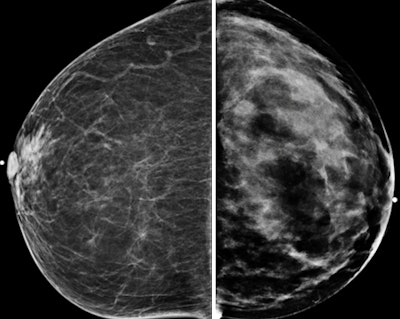

Craniocaudal mammograms of the same 70-year-old (left), rated type 1 density, and of the 42-year-old (right), rated type 4.The findings show not only that CT breast density readings were consistent with mammographic readings, but also that there was greater interobserver agreement at CT, the authors wrote. And if knowing a woman's breast tissue density helps optimize strategies for early cancer detection, CT could really help.